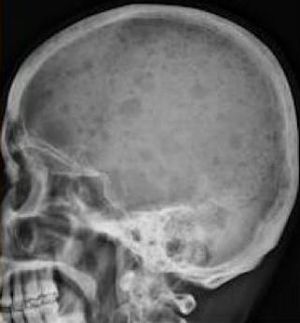

Multiple myeloma is cancer of monoclonal plasma cells, produces large amounts of IgG (55%) or IgA (25%), high levels of IL-6 may be present. It is the most common primary tumor arising within bone in the elderly. Symptoms are bone pain, hypercalcemia, and renal failure. It has poor prognosis as it may lead to renal insufficiency, ↑susceptibility to infection, anemia, and primary amyloidosis (AL). The skull radiograph shows numerous circular punched-out lytic lesion of the skull bone.